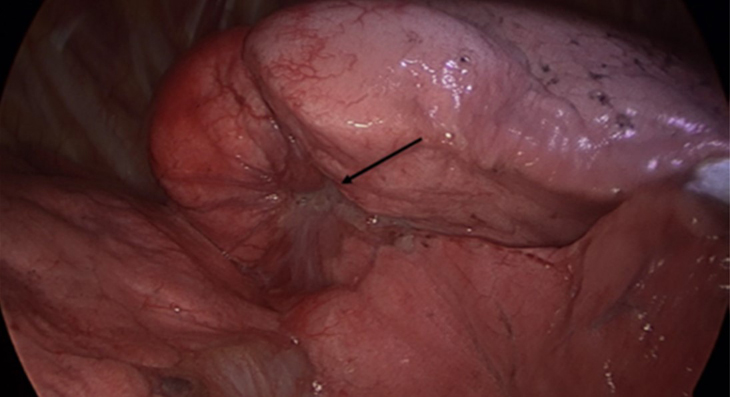

폐암 종괴의 모습으로 폐암의 육안 소견에 해당함. 제주대학교병원 제공

| 폐암 종괴의 모습 |